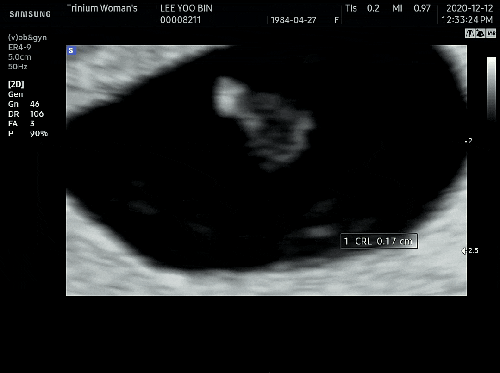

임신 6주-9주 초음파 사진 영상 이에요~

안녕하세요~ 임신 6주차 기록을 이제 남겨요~ 6주부터 본격적인 입덧으로 입덧 캔디와 새콤달콤을 달고 살...